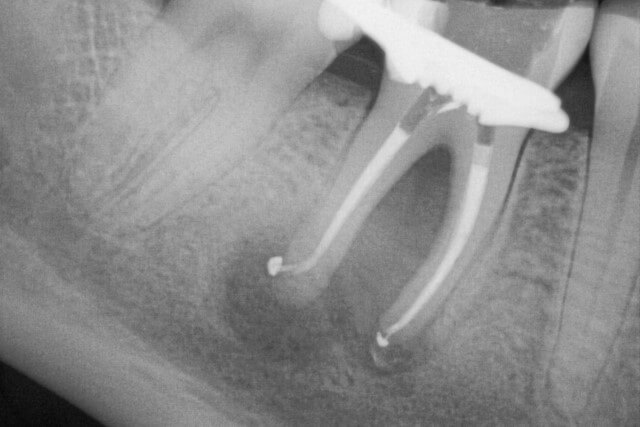

Zahn mit ausgedehnter Entzündung an der Wurzelspitze (dunkler Bereich)

Wurzelfüllung am Tag der Wurzelbehandlung

Abheilung der Entzündung nach einem Jahr